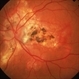

- central disciform scar

- Fundus photograph and OCT scan of an 86-year-old man with long-standing type I diabetic proliferative retinopathy.